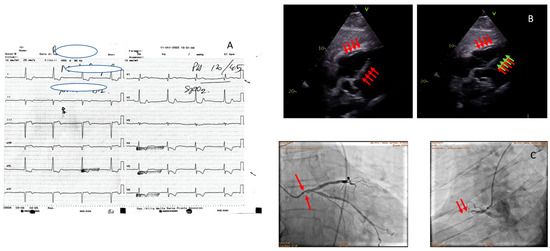

| Papillary muscle rupture and acute mitral regurgitation |

| Ventricular septal defect |

| Rupture of the ventricular free wall |

| Pseudoaneurysm |

| Left ventricular apex thrombosis |